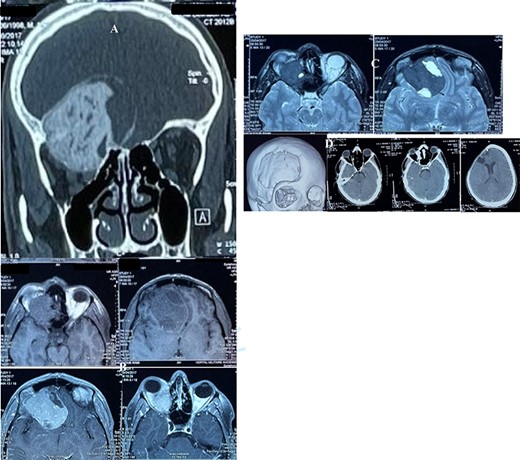

(A) CT scan, bone window, coronal reconstruction, showing well-defined ground glass lesion lying on the orbital roof invading the orbit and above the roof. (B) T1 weighted MRI images showing an expansile, heterogeneous and cystic lesion involving the orbital roof and invading the orbit below and the cranium above, with an enhancing after injection. (C) T2 weighted MRI images: the tumor is of a low intensity, whereas the cystic parts is hyperintense. (D) Postoperative CT scan, showing successful resection of the majority of the lesion.

The cerebral CT scan revealed a large heterogeneous mass with ground glass appearance, which lies in orbit extending to the roof of the right orbit and above the roof, associated with significant bony erosion (Fig. 1A). The lesion was reported radiologically as consistent with skull-base meningioma and less likely ossifying fibroma. On magnetic resonance imaging (MRI), the lesion was delineated more in detail (Fig. 1B–C).